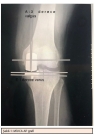

Doç.Dr Murat Saylık

Ortopedi ve Travmatoloji Uzmanı

GONARTROZ (DİZDE KİREÇLENME) VE UNİKONDİLERDİZ PROTEZİ İLE TEDAVİS...

The Learning Curve in Unicompartmental Knee Replacement Op.dr .Saylık M ...